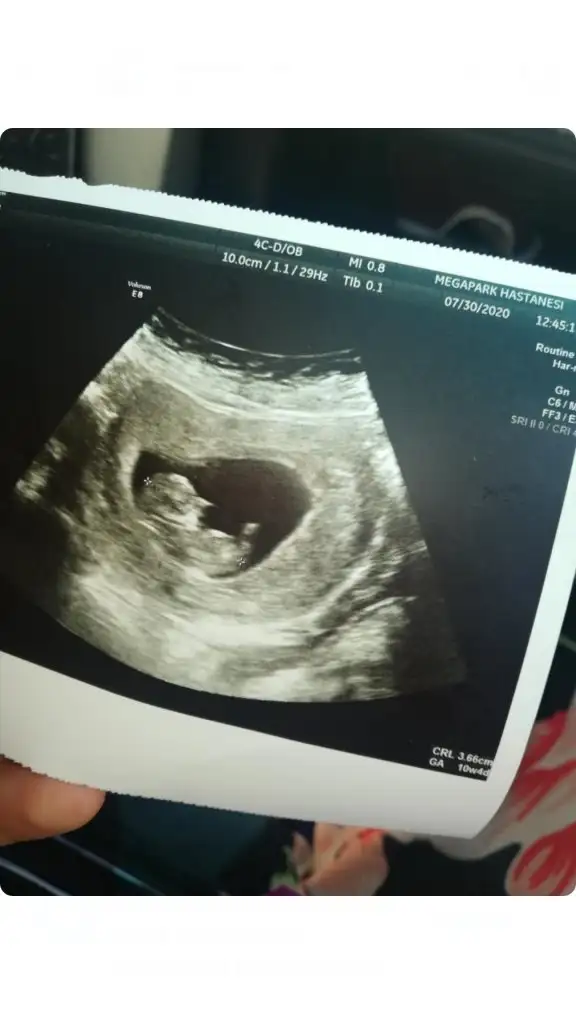

Tahmini olan varmı arkadaşlar 9 haftalık bebegim

Eklentiler

• 6278E112-C448-47F5-9E93-E9D9BB5F210D.webp

20,2 KB · Görüntüleme: 57